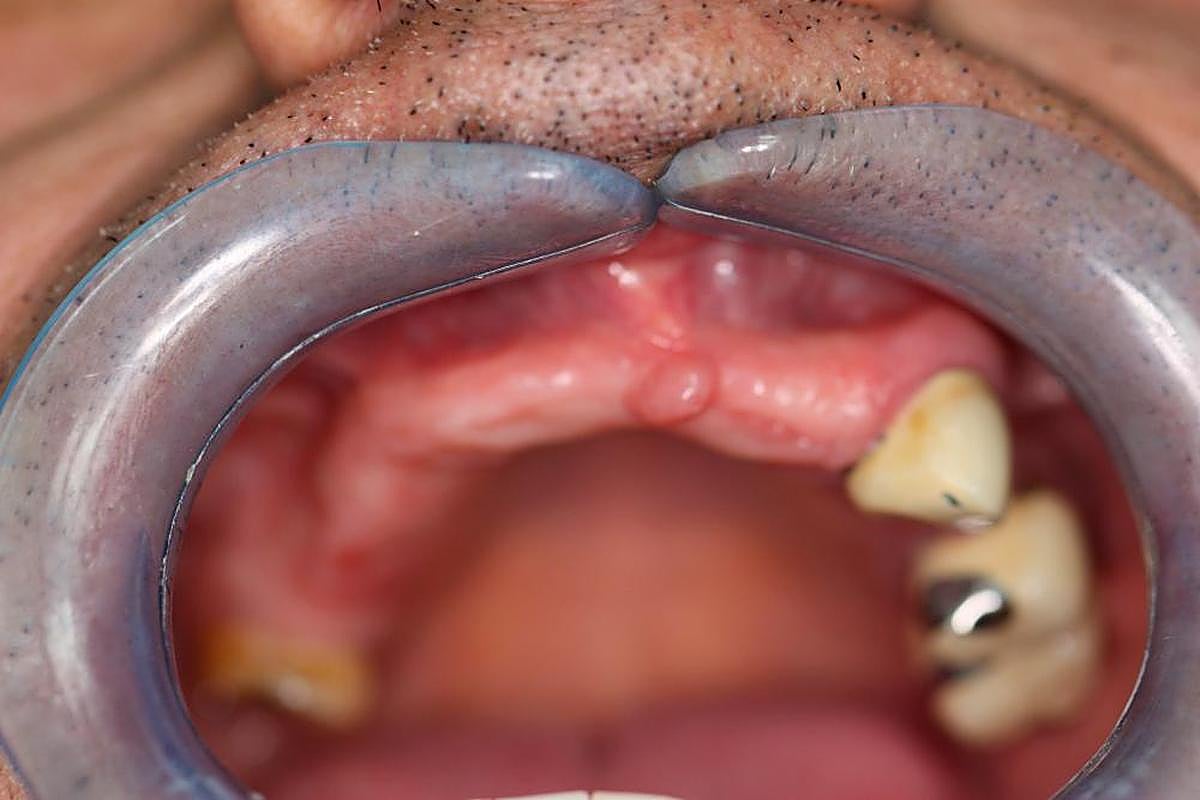

PASO 4. Inicio de la intervención.

PASO 5. Colocación de la férula en la boca para atornillar el cuerpo del implante y el pilar.